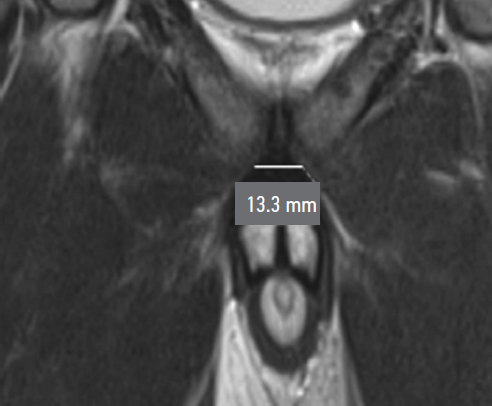

During preoperative assessment, penile length was recorded in both the flaccid and stretched states (median: 6.75 cm and 12 cm, respectively). Penile length in erection was measured by the patient at home (median: 12.5 cm). All patients underwent pelvic magnetic resonance imaging (MRI) to assess the topographic anatomy of the penile suspensory apparatus preoperatively. The following parameters were recorded: length and width of the suspensory ligament (median: 2.7 cm and 1.4 cm, respectively), thickness of the subcutaneous fat layer (median: 2.85 cm), angle of ligament divergence in the frontal plane (median: 65.8°), and the angle between the corpora cavernosa and the pubic symphysis (median: 17.42°) (Fig. 1–Fig. 5).

Fig. 2. Width of the penile suspensory ligament.